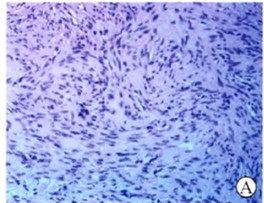

病理巨检:结节一个,大小为3cm×2.5cm×2.5cm,无包膜,肿瘤境界清楚,切面灰白色,均质实性,质地柔韧,无出血及坏死。镜下观察:肿瘤由分化好的梭形细胞组成,边界清楚,胞质丰富,深粉红色;核呈杆状,两端钝圆,染色质细腻,无异型,无核分裂象,无坏死,瘤细胞聚集成束,呈编织状排列(图2A)。免疫组化:desmin+(图2B、2C),SMA+,Vimen.tin+,NSE-,Bcl-2-,CDll7-,S-100-,CD34-。

图2A 肿瘤由分化好的梭形细胞组成,边界清楚,胞质丰富,深粉红色;核呈杆状,两端钝圆,染色质细腻,无异型,无核分裂象,无坏死,瘤细胞聚集成柬,呈编织状排列(HE×100)